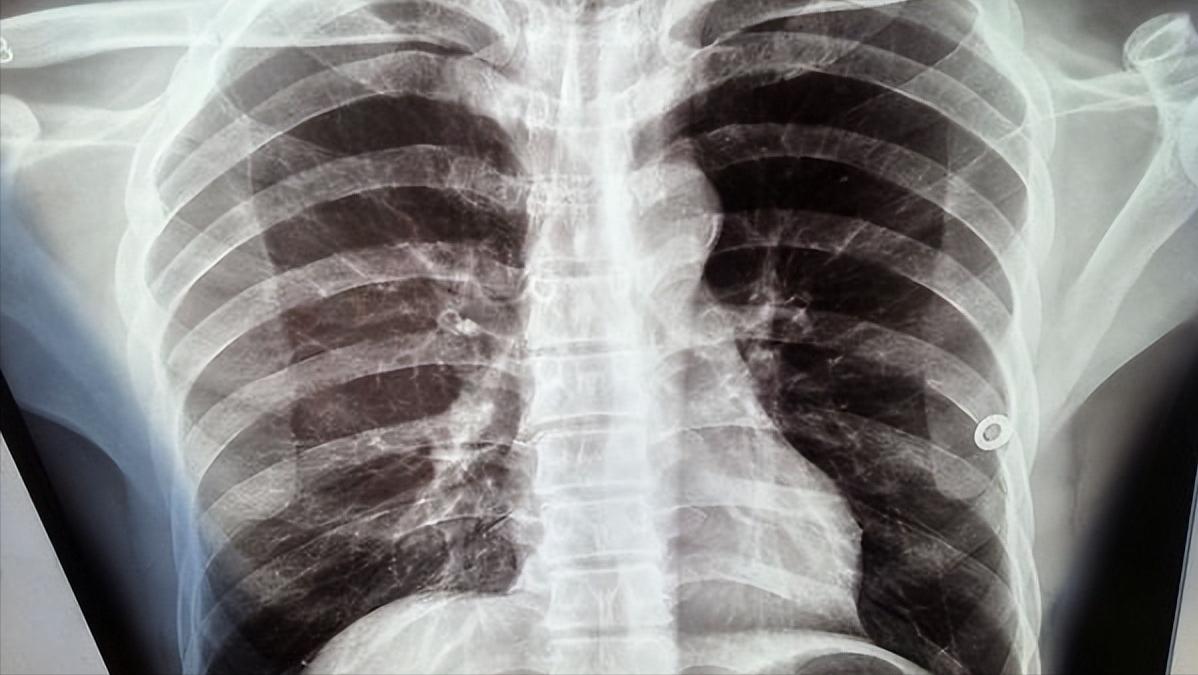

小张两天前急忙到当地医院查胸部CT,结果显示:右侧胸腔积液。

这一下小张彻底慌了神,为了进一步治疗疾病,于昨日来我院就诊。经过一系列鉴别诊断,现已以“结核性胸膜炎”收入我院。